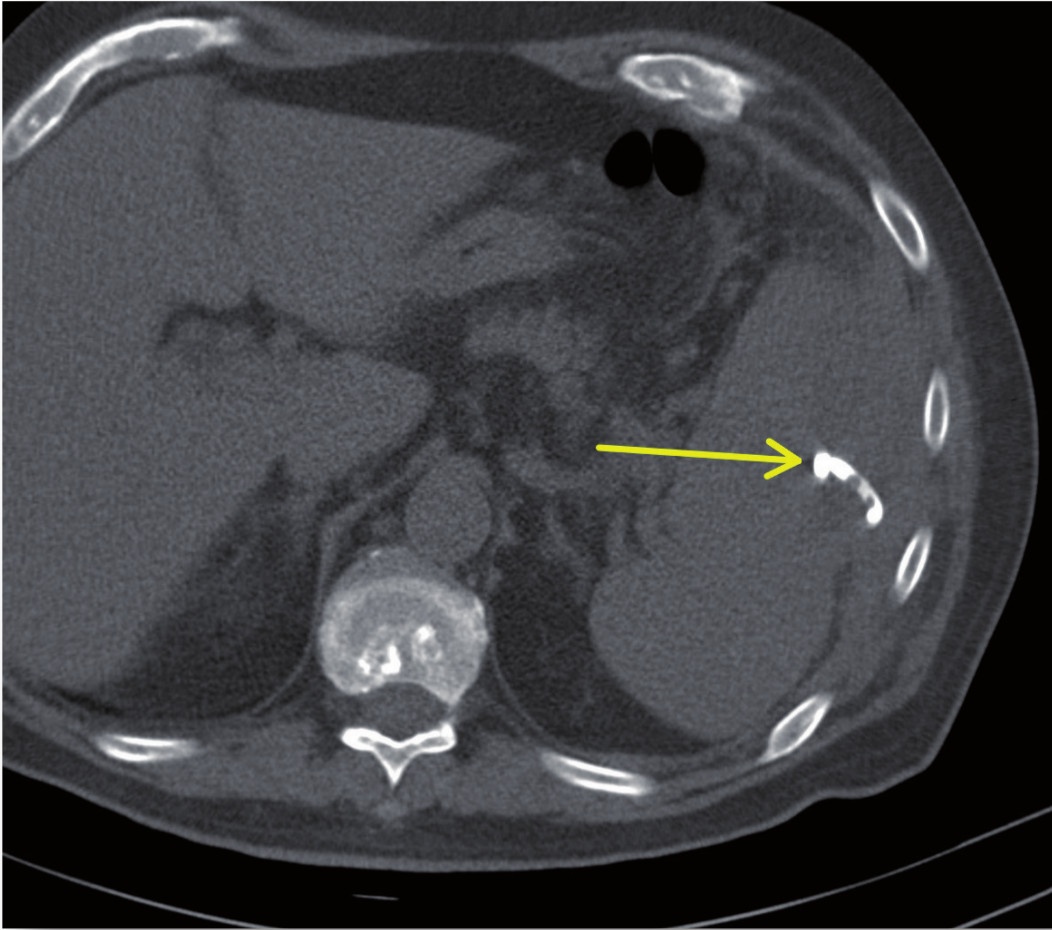

in Seldinger-Technik: Dargestellt ist die Kontrolle des intercostalen

Zugangsweges (Pfeil).

Im interdisziplinären Konsens erfolgte noch am selben Tag die interventionelle Therapie mittels CT-gestützter Drainageneinlage. In Rückenlage wurde nach Lokalanästhesie unter sterilen Kautelen in Seldinger-Technik CT-gesteuert ein 12F-Pigtailkatheter implantiert (Abbildung 2). Hierbei entleerten sich 240 ml einer eitrig-trüben übelriechenden Flüssigkeit. Proben zur mikrobiologischen Diagnostik wurden asserviert. In der abschließenden computertomografischen Lagekontrolle zeigte sich der Milzabszess vollständig entleert und kollabiert (Abbildung 3).